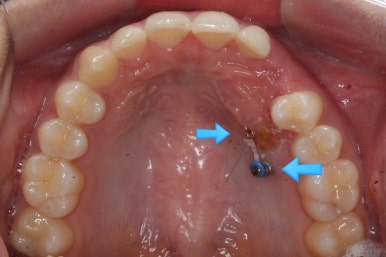

부산매복치아교정 키다리아저씨치과에서 소수술을 마친 모습입니다.

우선 남아있던 유치는 발치를 했고, 매복 송곳니에 장치를 붙인 후 잇몸 밖으로 체인 형식의 연장선만 빼놓았습니다. (두 개의 화살표 중 위쪽 화살표) 매복치아를 적절한 방향으로 요리조리 당겨줘야 하기 때문에 미니스크류를 이용했습니다. (두 개의 화살표 중 아래쪽 화살표)

수평으로 누워있었던 송곳니의 각도가 바로 잡힐 때까지는 계속 미니스크류만을 이용해서 당겨줍니다. 치아는 뼈속에서 헤엄치듯이 조금씩 방향을 잡아갑니다.